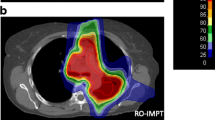

Figure 2 shows representative dose distributions for the 3-phase SFUD and IMPT plans. It shows the dose distribution for CT40%, CT50%, CT60%, and 4DDD. In the modeling of 4DDD calculation algorithm, the MU of a spot delivered at a given time is divided into adjacent-phase CTs with weighted factors considering the remaining breathing times of each phase. Due to the specification, the dose at the center phase CT (CT50%) tended to increase than the other phases. In contrast, the dose at the CT60% (the end of gating) decreased because the delivery spots may be less than the other phases owing to the combination of the synchrotron operation pattern and the breathing motion pattern. Figure 3 shows a comparison between SD and 4DDD for the 5-phase plans.